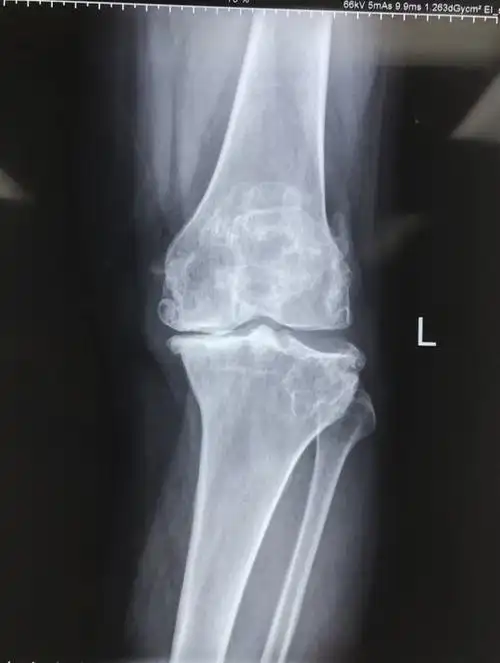

48岁男性膝盖内侧有异常凸起

8 膝内翻x片.jpg

应用缩小胫骨平台截骨技术矫正膝内翻畸形的探讨